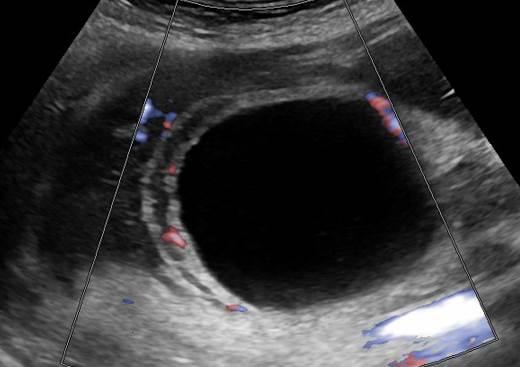

Viêm túi mật

Viêm túi mật - Ảnh 2

Viêm túi mật - Ảnh 3

» Thông tin: Nữ giới – 88 tuổi.

» Lâm sàng: Đau mạn sườn phải / Sốt.